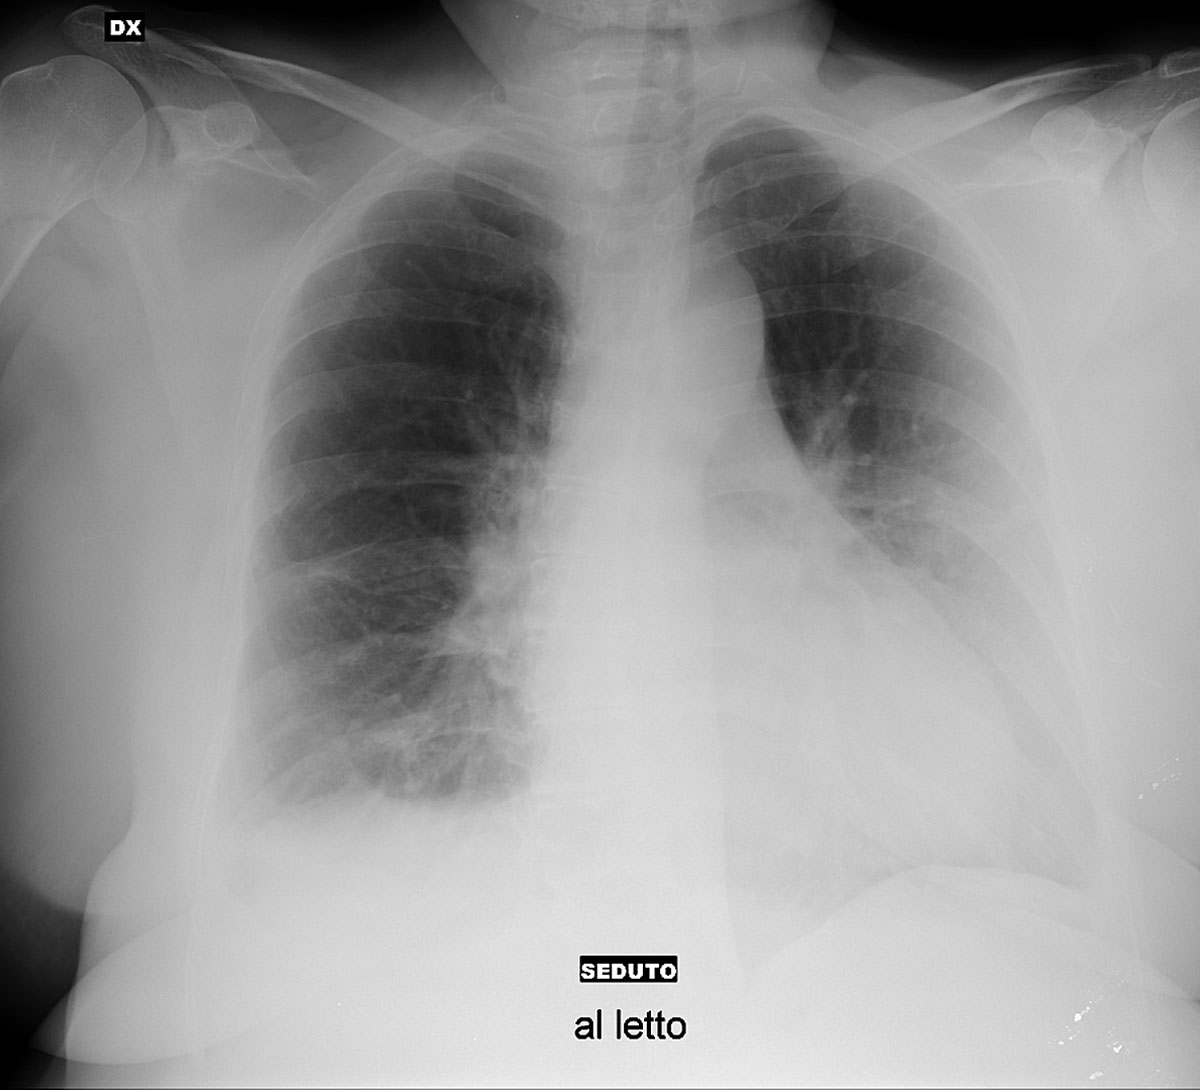

On 16 March 2020, analysis of arterial gases showed a pH of 7.41, a pO2 of 73 mm Hg (9.73 kPa) and a pCO2 of 38.9 mm Hg (5.1 kPa). The second anteroposterior chest x-ray (fig. 2), taken with the patient sitting in bed, showed a reduction of the density and extent of the parenchymal opacities seen on admission at the right base and the left hemithorax in the previous image. Patient 1 left the hospital the same day.

Figure 2 chest x-ray of patient 1 on day 6 after admission, 16 March 2020. Courtesy Ospedale di Sassuolo. It shows a marked reduction of the opacities noted in figure.1 (see detailed radiological description in the text).